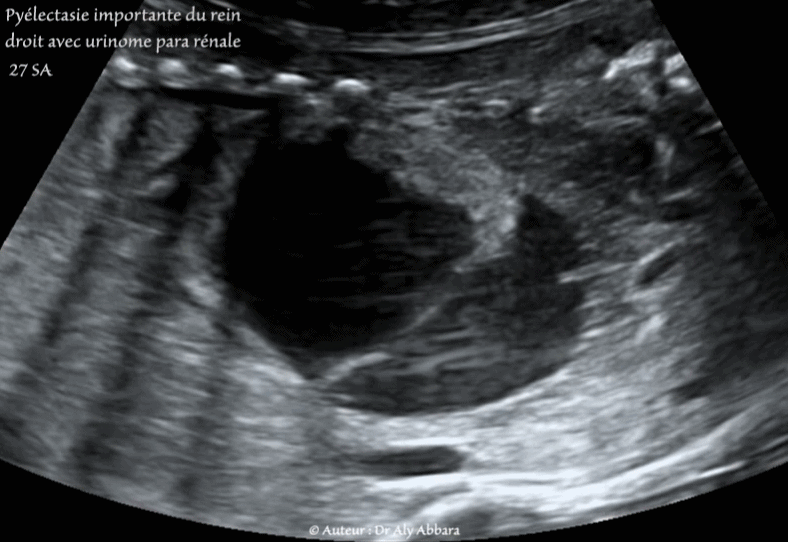

Vidéo et images échographiques (balayage droite-gauche) montrant une sévère pyélectasie unilatérale (à 34 mm) du rein droit compliquée par la lamination puis la rupture du cortex rénal à l'origine de la formation d'un urinome para-rénal.

Rein gauche et vessie normaux.

Grossesse de 27 SA ; foetus du sexe masculin.